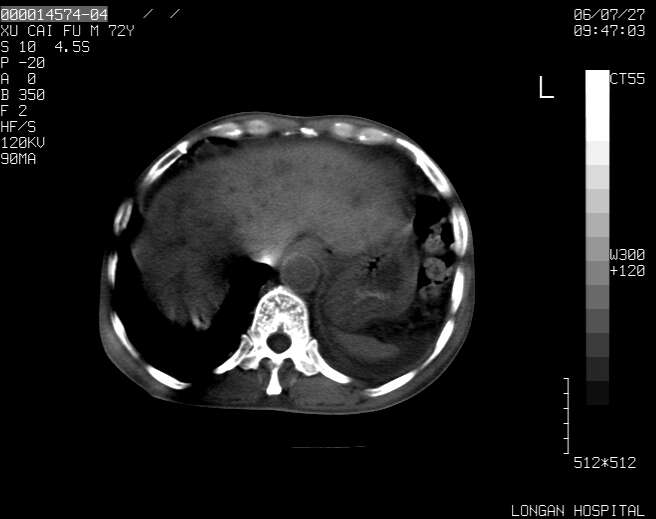

以下是引用winter在2006-7-30 20:14:00的发言:[br]1、考虑胆囊癌伴胆道侵犯并高位胆道梗阻、肝内多发转移、腹膜后淋巴结转移。[br]2、右肾轻度积水。[br]3、老人家72岁了胰腺头体尾部均较饱满,不过未见密度异常及其他异常征象。[br]4、腹水。

以下是引用jiajie在2006-7-31 7:10:00的发言:[br]考虑肝转移瘤,腹膜后淋巴结增大。[br]胃癌不能除外,建议胃镜检查。